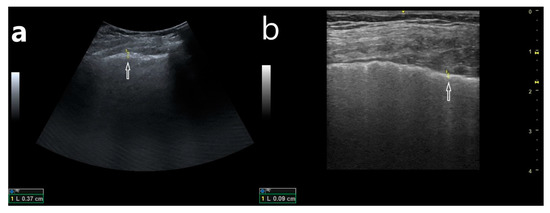

- (1)

- Abnormalities within the pleural line (thickened, irregular, fragmented);